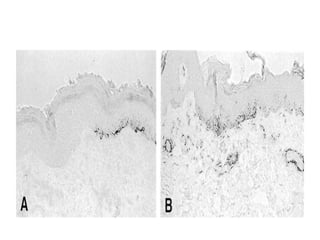

HMB-45 staining of minigrafts of non-responders

showing a sequential decrease of melanocytes

from day 14 (a), 17

(b) and 21 (c), with a complete disappearance on

day 28 (d). Meanwhile, keratinocytes show

striking cytoplasmic vacuolation.

Day 14

Day 17

Day 21

Day 28